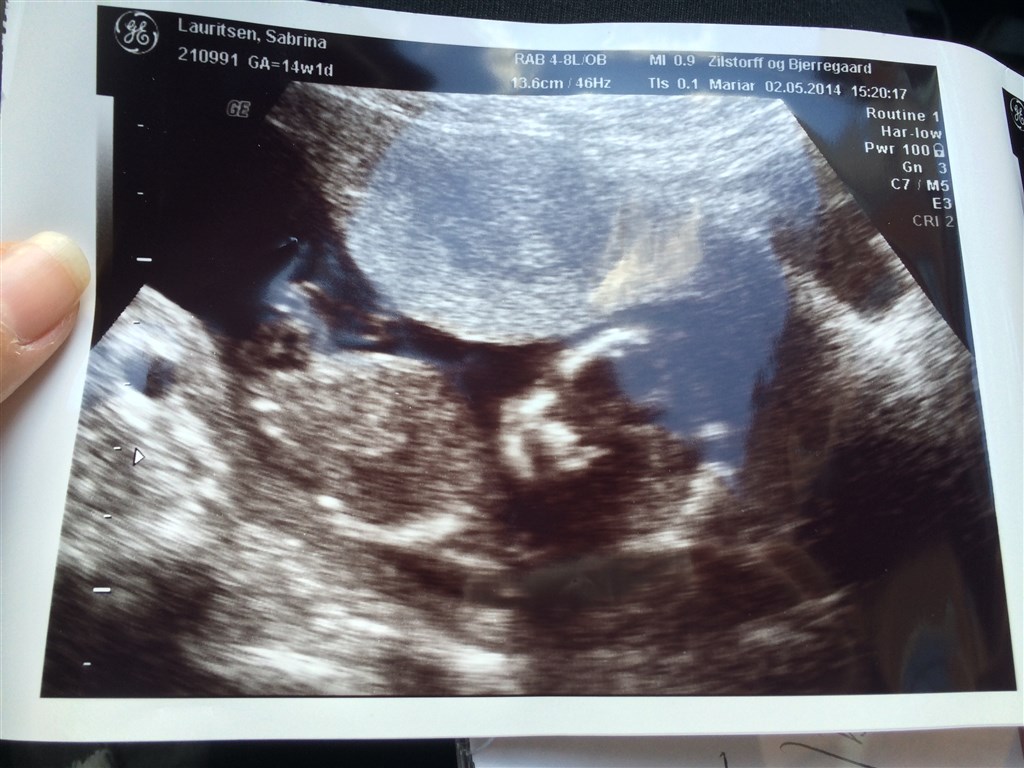

Jeg har lige været inde hos scanningskliniken på Østerbro, hvor jeg fik 99% sikkerhed på at jeg ..... Venter mig en lille pige!

Der var kun 1% for at der var en dreng, men jeg har selvfølgelig fået en ny tid for den sidste procent.. Men jeg kunne godt begynde stille og roligt at købe lyserøde ting :-)

Vedhæftede fotos (klik for at se i fuld størrelse)

Der står 14+1 på billederne